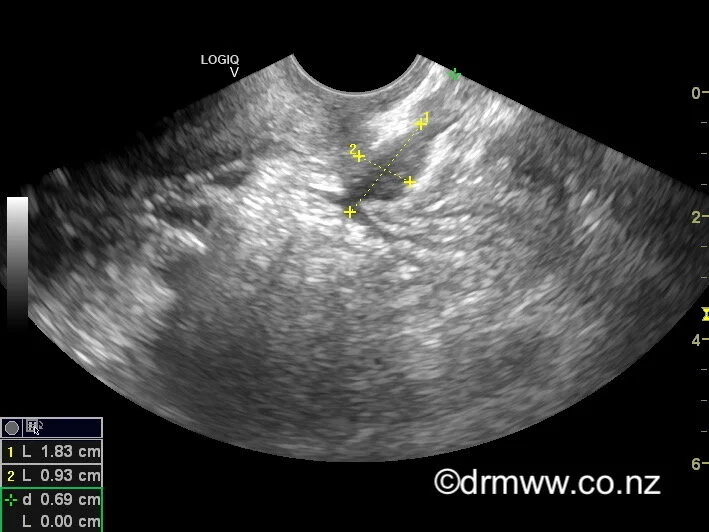

Unfortunately, there is no simple screening test (such as a blood test) for endometriosis. Dr Wynn-Williams can perform transvaginal ultrasound (see here) that can be very useful in the diagnosis of deep infiltrating endometriosis in the pelvis, bowel, and bladder. A negative ultrasound does not rule out that endometriosis is present. MRI can also be useful but can be expensive. Ultimately, to make a diagnosis of endometriosis, Dr Wynn-Williams will rely on listening to each woman’s symptoms, the effects these symptoms are having on her life, and the examination findings.

Rectal Muscularis Endometriosis nodule seen on TVUS